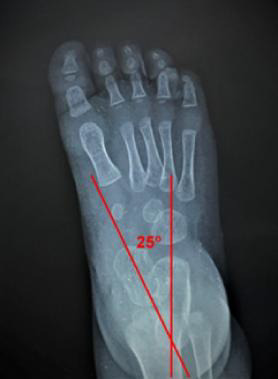

Results: Data from thirty articles included in this review were arranged into different subheadings. In the anteroposterior view (AP), assessment of the hindfoot deviation was by the AP talo-calcaneal angle (Kite's angle); the forefoot and midfoot for abduction and adduction alignment was by the AP talo-first metatarsal angle, the talo-second metatarsal angle, the calcaneo-second metatarsal angle, the calcaneofifth metatarsal angle; the forefoot and midfoot rotation was by observing the normal proximal convergence of the metatarsal bones axes. In the lateral view, assessment of the hindfoot sagittal plane alignment was by the lateral tibio-calcaneal angle; hindfoot varus or valgus deviation by the lateral talo-calcaneal angle; talus bone alignment by talar declination angle and the tibio-talar angle; calcaneal bone alignment by the calcaneal inclination angle and the tibio-calcaneal angle, the midfoot and forefoot sagittal plane alignment for the plantar arch by the lateral talo-first metatarsal -Meary's- angle, the calcaneal inclination angle, and the lateral calcaneofirst metatarsal -Hibbs- angle; forefoot and midfoot rotational alignment by observing the overlap shadows of the metatarsals' shafts and drawing their axes.

Conclusion: Drawing certain lines and angles with a systematic approach to assess different regions of the foot in the radiographic films of children can facilitate the process of assessment of the foot (as a whole) for deformities.